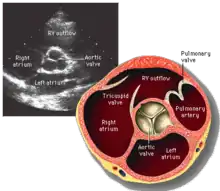

La valve aortique est l'une des quatre principales valves du cœur. Elle sépare le ventricule gauche de l'aorte. Elle est constituée de trois cuspides. Au cours du cycle cardiaque, elle s'ouvre et se ferme régulièrement. Lorsqu'elle est ouverte, elle permet le passage de sang du ventricule gauche ; lorsqu'elle est fermée, elle empêche le sang de refluer vers le ventricule. Les dysfonctionnements qui peuvent la toucher sont le rétrécissement aortique et l'insuffisance aortique. L'examen qui permet leur évaluation est l'échographie cardiaque.

La valve aortique est située entre la chambre de chasse du ventricule gauche et l'aorte ascendante. Elle est constituée de trois cuspides semi-lunaires. Les cuspides sont des replis d'endocarde sur une lame fibreuse attachée à la paroi du ventricule gauche et de l'aorte. Les cuspides soutiennent les trois sinus de Valsalva, qui sont trois renflements de la partie initiale de l'aorte, desquels naissent les deux artères coronaires.

L'échocardiographie permet de visualiser la valve aortique, d'étudier sa morphologie et son fonctionnement.